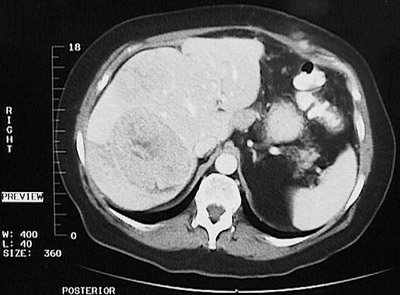

| This axial view abdominal CT scan demonstrates a large irregular mass in the right lobe of the liver. This is an hepatocellular carcinoma. Worldwide, the most common antecedent to development of this neoplasm is hepatitis B infection. Now that testing for hepatitis C is available, more of these cancers have been associated with this infection. |